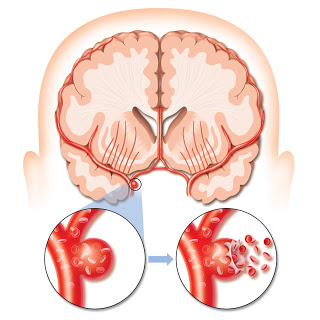

뇌경색의 주된 이유가 되는 것은 혈전이지요. 혈전이란 혈관 속에 피가 굳어진 덩어리를 얘기하는데 이것이 혈관을 막는 것이 뇌경색에 큰 영향을 줄 수 있습니다. 평균적으로 많이 발생하는 연령대는 5~60대이지요. 뇌경색은 양쪽 뇌에 모두 나타나는는 것이 아니라 주로 한쪽 뇌에만 발생하지만, 주로 한쪽 팔다리가 마비되었다거나 얼굴 근육이 굳어버리기도 해요. 그렇기에 뇌경색 초기증상이 발생한다면 민첩하게 대응를 해야 하겠습니다.

또 뇌경색의 까닭은 혈관의 협착을 유발시키는 동맥경화증이고요. 동양에서는 뇌내동맥경화증이, 서양에서는 경동맥동맥경화증이 많이 나타나고다. 그리고 흡연, 고지혈증, 당뇨병, 고혈압, 건강에 옳지 않은 식습관, 스트레스 등도 뇌경색을 발생시키는 위험요인입니다.모든 질병에 단일 이유가 되는 것이 없듯이 뇌경색도 단일 이유가 되는 것이 아닐 수 있고요.